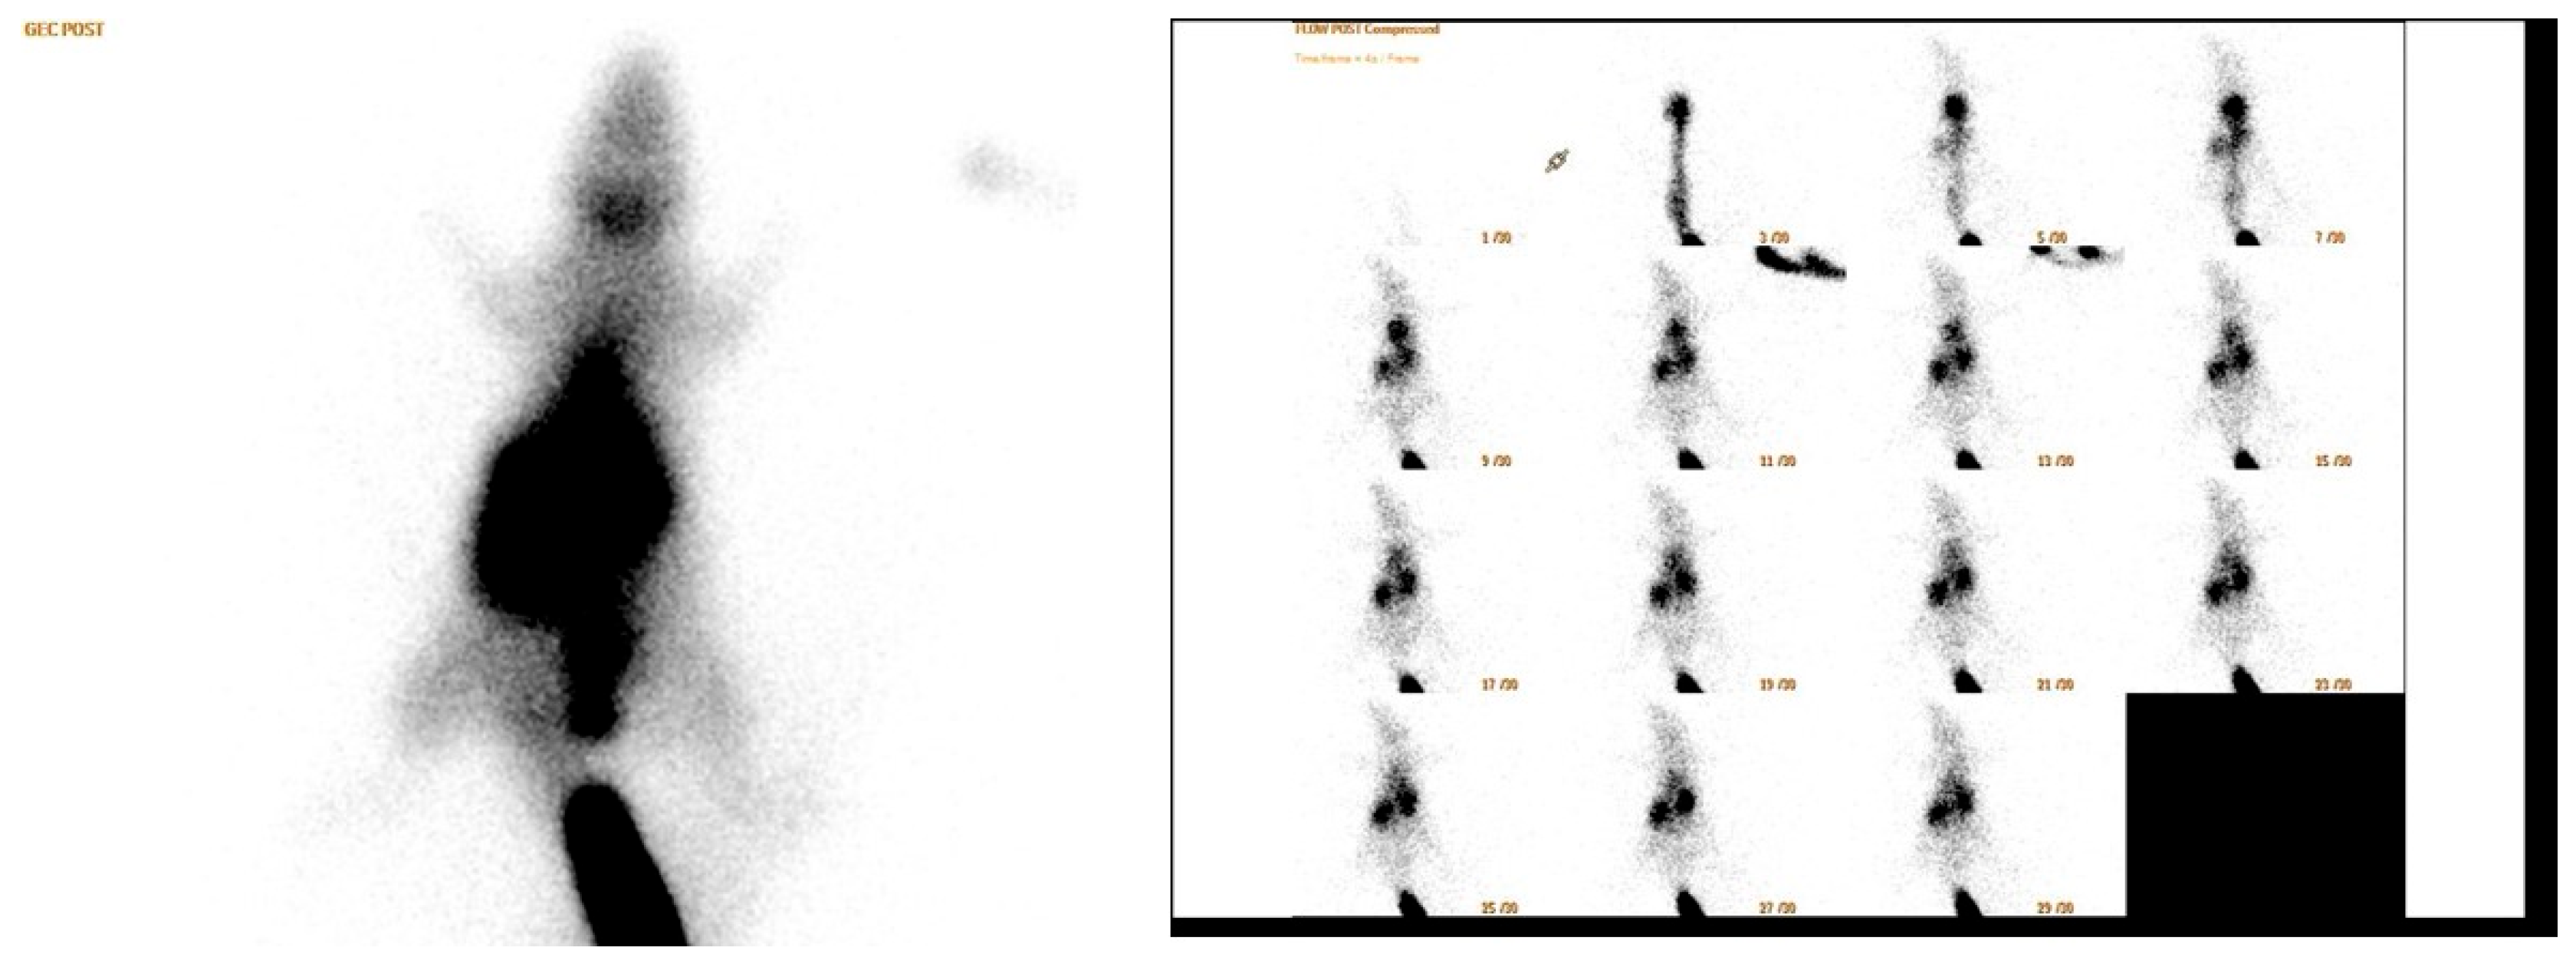

Anaesthesia was induced with ketamine (90 mg/kg body weight) and xylazine (10 mg/kg body weight) administered intraperitoneally. On postoperative day 14, rats were placed prone under a single-head SPECT/CT gamma camera (Philips Brightview XBT; Cleveland, OH, USA). A dose of 1 mCi (37 MBq) of Tc-99m-methoxyisobutyl isonitrile (MIBI) was injected into the tail vein of each rat under each camera (Figure 4). A low energy general purpose collimator (LEGP) was used for all scintigraphic imaging procedures. First, dynamic blood perfusion images were acquired in a 128 × 128 matrix in 1 min in 30 frames of 2 s, starting simultaneously with the injection. Then, early phase static blood pool images were acquired in a 256 × 256 matrix for 5 min after the dynamic images. Finally, the late static phase was acquired in a 256 × 256 matrix for 5 min 30 min after injection. All rats underwent surgery on the right leg. Therefore, all images were taken on the right side of the mark. After the images were obtained, a region of interest (ROI) of equal size was drawn on the surgical site at the location of the Achilles tendon and gastrocnemius muscle and on the contralateral leg of each rat in the early and late images. Counts in the ROI were calculated automatically. In addition, in the early and late static images, the total body count was calculated by drawing the ROI over the whole body of the rat. In this calculation, the activity remaining in the tail vein was excluded from the ROI. The images obtained were first evaluated visually by a specialist in nuclear medicine (Figure 5). Quantitative evaluation was performed using four parameters. The formulas for these parameters are as follows:

Figure 5. Scintigraphic images.